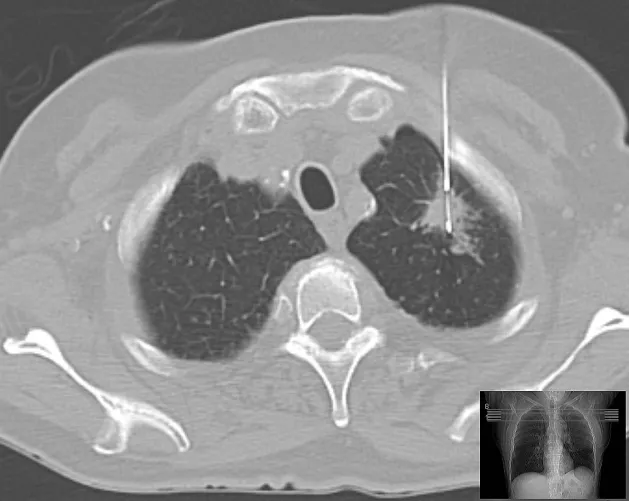

Gyanús szövetszaporulat biposziája tüdőben.

CT-vezérelt biposzia tüdőrákra gyanús képletben – szerző: Hellerhoff, liszensz: CC BY-SA 3.0 (Wikimedia Commons)